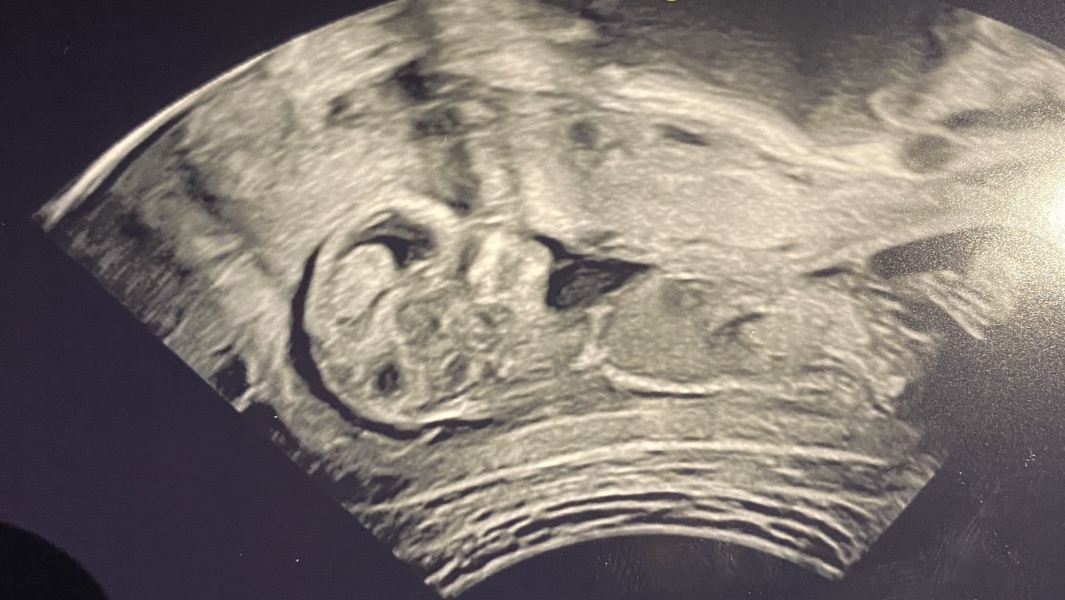

cheekysausage · 23/10/2022 22:18

Hi all, another scan! Is the nub any clearer on this one?!

Gilm0reGirl · 23/10/2022 22:20

@cheekysausage no nub from what I can see but that scan is amazingly cool!